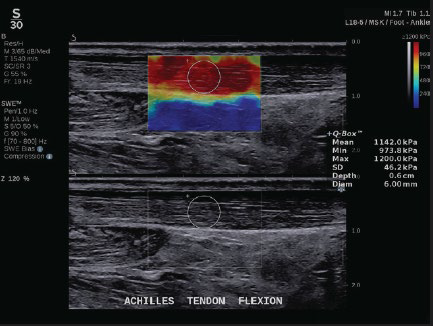

(2)進化したSWE PLUSTM イメージング

SUPERSONICTM MACH シリーズに搭載している独自技術ShearWaveTMElastography は、生体内を伝搬する剪断波の速度から弾性率を計算し、数値とカラー画像をリアルタイムに表示する。またプローブを走査する際、プローブで生体を圧迫する必要がないため、再現性にも優れる。

従来システムではSWE のレンジは800 kPa までだったが、SUPERSONICTMMACH シリーズでは最大1200 kPa まで測定が可能※となった。

※MSK プリセット使用時整形領域では腱や筋肉の硬さ、乳腺領域では腫瘍の硬さ、肝臓領域では、肝組織の硬さを評価することで、疾患の早期診断に寄与する。